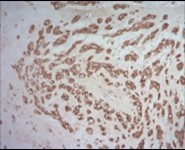

Figure 7.Parachordoma depicting immune reactivity to S100 protein 16.

Parachordoma is immune reactive to cytokeratin CAM 5.2 and glial fibrillary acidic protein (50%). A subset of tumour cells are immune reactive to CD99 and smooth muscle actin (SMA). Stroma is intensely highlighted with an alcian blue stain wherein staining intensity is reduced following hyaluronidase digestion. Tumour cells are immune reactive to epithelial membrane antigen (EMA), CK8/18, S100 protein, calponin (50%), vimentin, type IV collagen and CD117 6.

Tumour cells are immune non reactive to CK1/10, cytokeratin AE1/AE3, CK20, CK7, CK19, CK12-17,smooth muscle actin (SMA), muscle specific actin (MSA), carcino-embryonic antigen (CEA), desmin, CD34, CD31, CD10, glial fibrillary acidic protein (GFAP), p63, TFE3, melan -A, brachyury, Human Melanoma Black-45 (HMB-45), D2-40 and α- inhibin.

Type IV collagen is immune reactive, envelops clusters of tumour cells and articulates a nest- like appearance 6, 7.